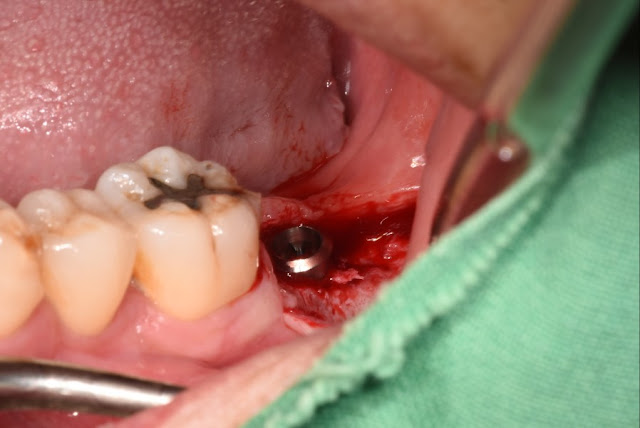

I removed the tooth using a trephine bur. A few months later, it will be replanted with a slightly larger fixture.

This is the last detention. We selected the location using a guide. It's convenient even if you can't see.